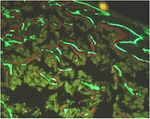

Mechanical homeostasis in living organisms ensures that our supporting structures such as the skeleton, the articular joint, the ligaments, the muscle and the tendons are continuously achieving an optimized balance between mechanical competence and light design. This process is controlled by the tissue resident cells, which can sense the mechanical environment through their extracellular matrix and can modify it according to some inbuilt homeostatic set points. The importance of this process becomes immediately evident when it goes wrong. This is the area of interest of the pathomechanobiology research. Osteoporosis and osteoarthritis are the two most common skeletal diseases in the elderly population and are both diseases of impaired mechanical homeostasis. Their consequences are catastrophic for the patients and usually involve prosthetic intervention, permanent disabilty and pain. The mechanisms regulating mechano-sensing and mechano-adaptive remodelling are not completely understood and even less is known about the interaction between the mechano-adaptive response and hormonal unbalance, inflammatory conditions and age-related conditions.